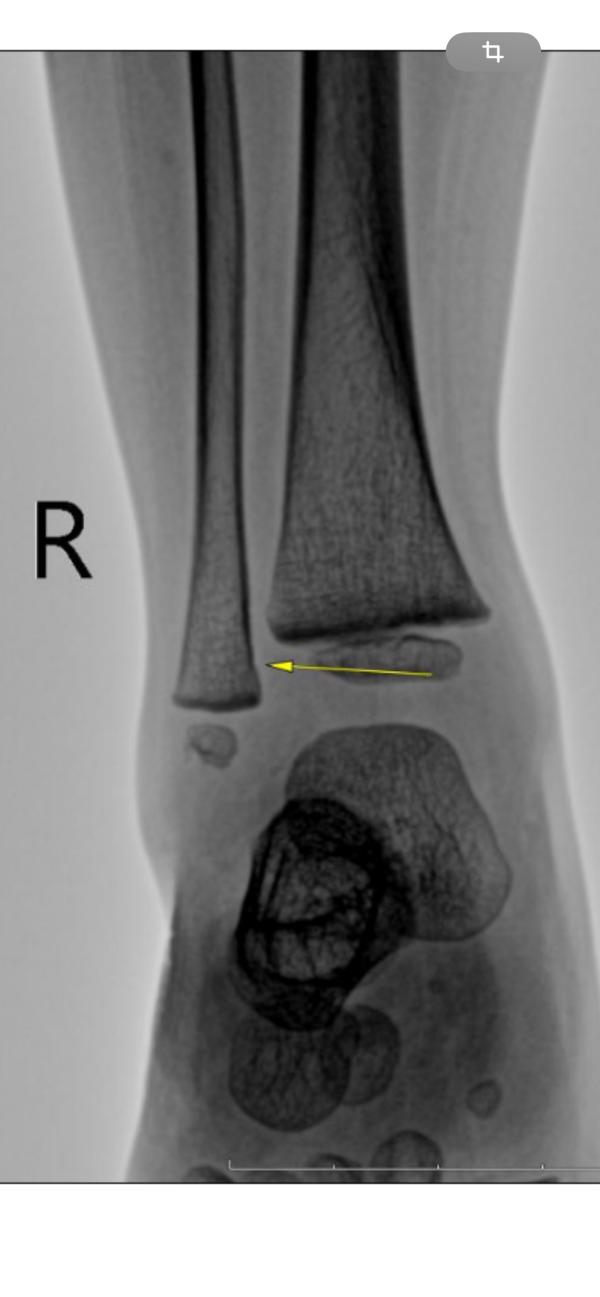

Sos! У кого у детей был диагноз «краевой перелом дистального отдела малоберцовой кости»???

Гипс не наложили, но и покой соблюдать нужно. Как с двухлеткой это соблюсти??? И с гипсом жопа и так😵💫🙈